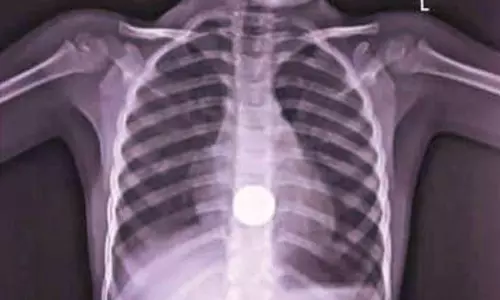

திருப்பூர் மாவட்டம், ஊத்துக்குளி ஒன்றியம், பல்லகவுண்டம்பாளையம் அருகே நேற்று முன்தினம் இரவு வீட்டில் விளையாடிக்கொண்டிருந்த 5 வயது குழந்தை தனது கையில் கிடைத்த 5 ரூபாய் நாணயத்தை வாயில் போட்டு விழுங்கி விட்டாள். நாணயம் தொண்டையில் சிக்கிக் கொண்டதால் அந்தக் குழந்தை தொண்டையைப் பிடித்துக்கொண்டு சத்தம் போட்டு அழுதாள்.

குழந்தையின் பெற்றோர் உடனடியாக பல்லகவுண்டம்பாளையத்தில் உள்ள ஒரு தனியார் மருத்துவமனைக்கு குழந்தையை கொண்டு சென்றனர். அங்கு குழந்தைக்கு எக்ஸ்ரே எடுத்து பார்த்ததில் உணவுக்குழாயில் 5 ரூபாய் நாணயம் சிக்கி இருப்பது தெரிய வந்தது.

அதனைத்தொடர்ந்து குடல் இரைப்பை அறுவை சிகிச்சை மருத்துவர் மற்றும் மயக்கவியல் நிபுணர்கள் கொண்ட குழுவினர் எண்டோஸ்கோபி சிகிச்சை மூலம் நாணயத்தை வெளியே எடுத்தனர். அவர்களுக்கு பெற்றோர் நன்றி தெரிவித்துக்கொண்டனர்.